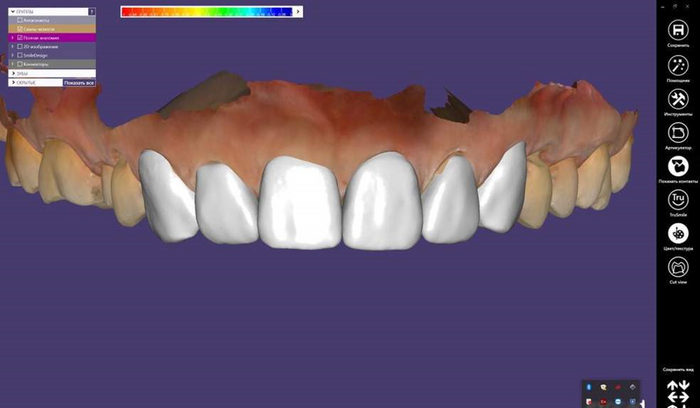

2 . Временная коронка лабораторная (длительного ношения, временная фрезерованная или коронка PMMA(полиметилметакрилат)\PEEK(полиэфирэтилкетон))

Изготавливается уже в зуботехнической лаборатории на фрезерном станке.

Эта коронка идеальная, когда надо закрыть зуб на длительное время, чтобы потом в случае чего вернуться к лечению. Например, при лечении кист на разрушенных зубах. При таком лечении никто не может дать гарантию, что зуб получится спасти. Сперва его наблюдают на сроках до 1 года. Всё это время зуб должен функционировать должным образом, поэтому его перекрывают коронкой. Ставить в таких случаях постоянную коронку не всегда гуманно по отношению к кошельку пациента, так как зуб в итоге может пойти под удаление. Тут как раз она будет идеальным решением, так как стоит в несколько раз дешевле.

Также эту корону используют при исправлении прикуса и лечении сустава, так как она легко корректируется во всех смыслах. Её можно не только подпиливать, но и добавлять материал прямо в кресле врача. Подобной коронкой можно и моделировать контур десны, в том числе и вокруг имплантов.